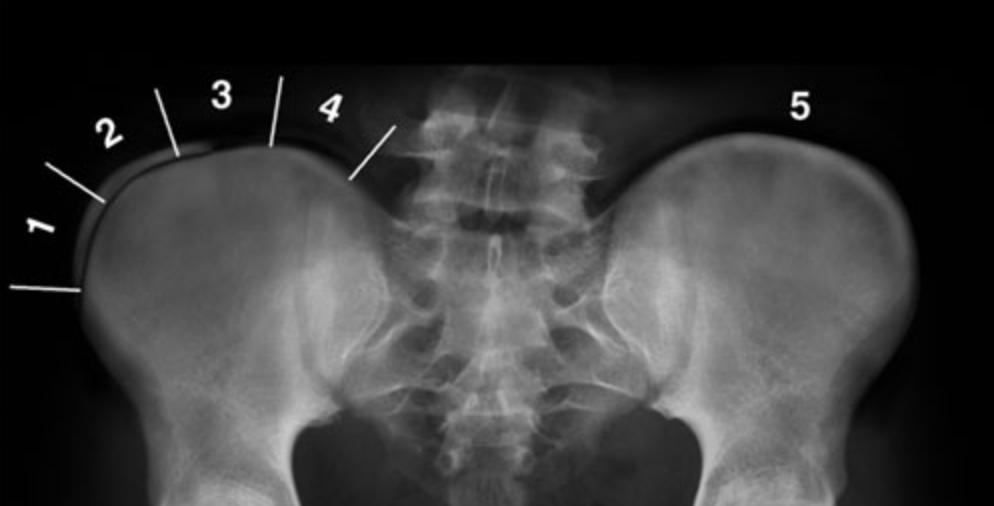

Stade de Risser

- permet de prédire si la scoliose risque de s’aggraver (Risser bas) ou se stabiliser (Risser haut)

- La différence entre Risser 4 et 5 est la fusion du noyau avec l’ilium